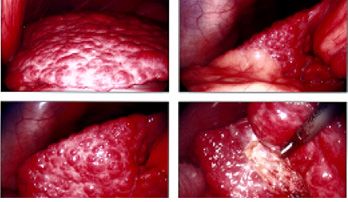

Liver Cirrhosis

picture of Liver Cirrhosis show enlarged image picture of Liver Cirrhosis